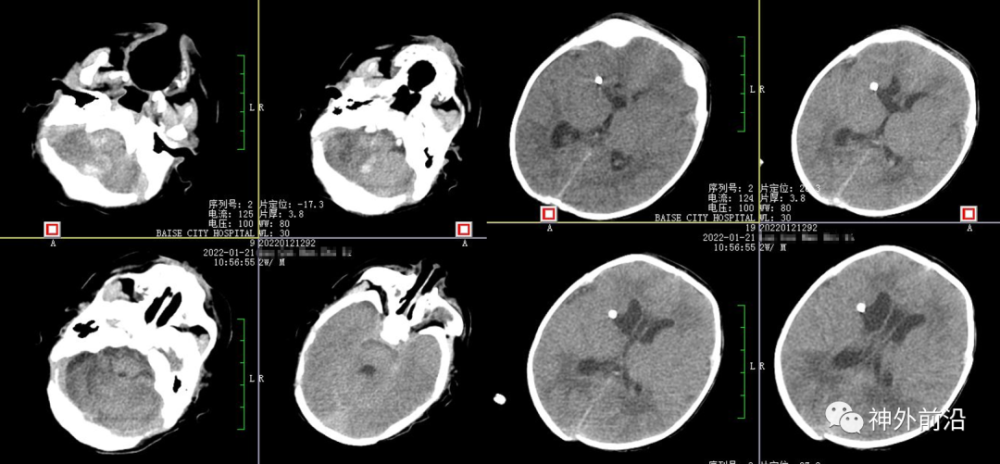

10.术后9天复查CT,拔除侧脑室引流管

11.术后17天复查CT

12.术后23天MRI

黄礼德:本例新生儿出院的时候是脑室系统稍大,术后我们反复性腰椎穿刺术,出院前颅内压力正常,目前没有脑积水。我们复查磁共振未见间质性水肿,但是该病例手术才两个月左右,后期还要进一步随访才行。